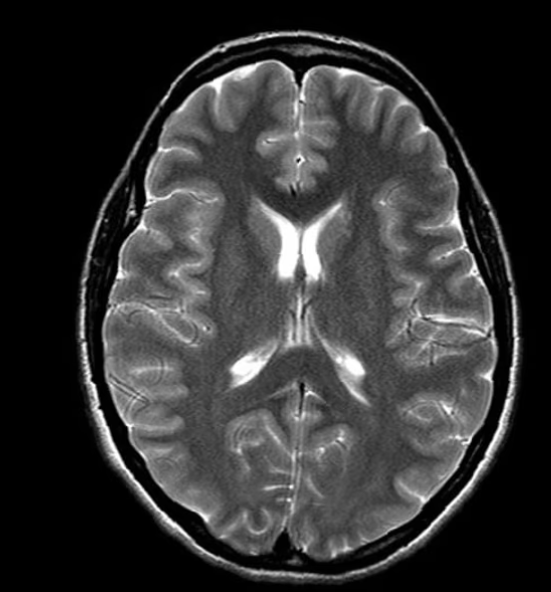

脑部MRI

多发性硬化与白质病变

脑部MRI第二意见

- 白质病变 — 它们意味着什么?

- 多发性硬化MRI第二意见

- 高级神经影像脑部MRI复查 · 复杂神经系统病例

- 复杂脑部病变诊断明确化